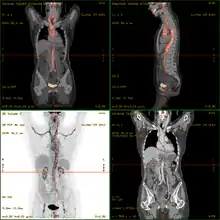

- 18F-fluorodeoxyglucose positron emission tomography/computed tomography (FDG-PET/CT)has become a widely used imaging tool in patients with suspected Large Vessel Vasculitis, due to the enhanced glucose metabolism of inflamed vessel walls.[11] The combined evaluation of the intensity and the extension of FDG vessel uptake at diagnosis can predict the clinical course of the disease, separating patients with favourable or complicated progress.[12]